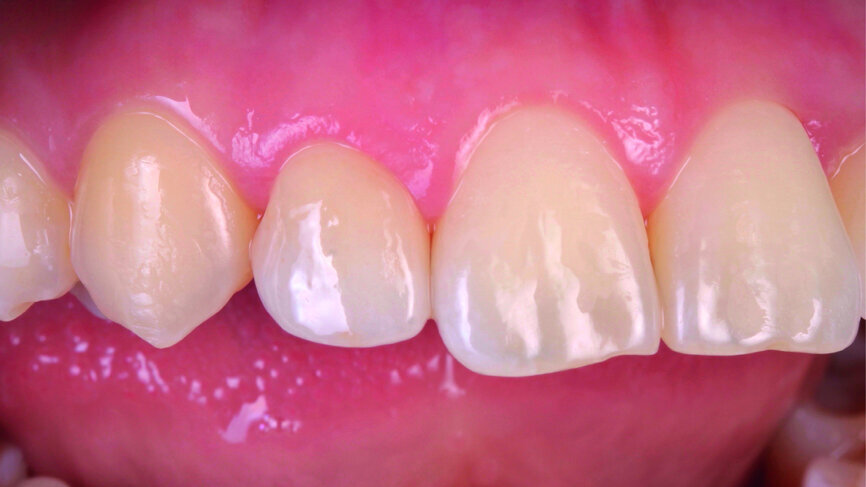

Fig. 1: The patient’s upper teeth before treatment.

Fig. 2: The patient’s upper teeth before treatment.

The clinical case features a female patient, who complained about missing tooth #22, as well as the shield-like shape of tooth #12 (Figs. 1 & 2). During the initial examination, the area around the missing tooth was estimated to be quite narrow for an implant. However, the patient declined orthodontic preparation, as she had already previously had orthodontic treatment with orthodontic surgery.